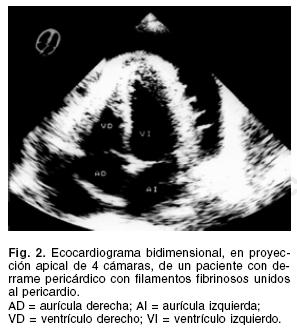

En dos (9.5%) el derrame pericárdico se asoció a la presencia de derrame pleural, y en uno (4.7%) había evidencia de infiltrado pulmonar apical derecho. El electrocardiograma cursó con anormalidades del segmento ST y ondas T invertidas en 80.9% de los pacientes, el resto no mostró cambios específicos. El ecocardiograma transtorácico identificó en todos los casos cavidades cardíacas en diámetros normales, con la presencia de derrame pericárdico. En 12 (57.1%) el derrame era de moderada cantidad, y 9 (42.8%) tenían un gran derrame pericárdico (Fig. 2). Hubo evidencia de engrasamiento pericárdico, con formación de puentes filamentosos y adherencias lineales en 7 de ellos. Existieron signos ecocardiográficos de taponamiento en 42.8% de los casos, que incluyeron compresión de cavidades derechas, dilatación de vena cava y variación respiratoria en las velocidades Doppler a través de las válvulas tricúspide y mitral. La tomografía computada de tórax se realizó en 15 pacientes. En todos hubo evidencia de derrame pericárdico (Fig. 3), 4 (26.6 %) casos tenían engrasamiento pericárdico, en uno había derrame pleural derecho y en otro un infiltrado parenquimatoso apical derecho.